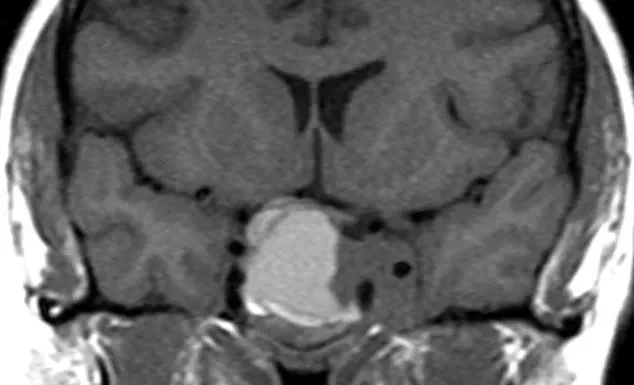

Posterior Fossa Tumors

Posterior Fossa Tumors Home At The Brain and Spine Centre, we specialize in the diagnosis and surgical treatment of neurological and spinal disorders. Dr. Muhammad Aqeel Natt, a leading neurosurgeon in Lahore, provides advanced, safe, and compassionate care for patients. Posterior fossa tumors require prompt, expert diagnosis and specialized surgical treatment to relieve symptoms and […]